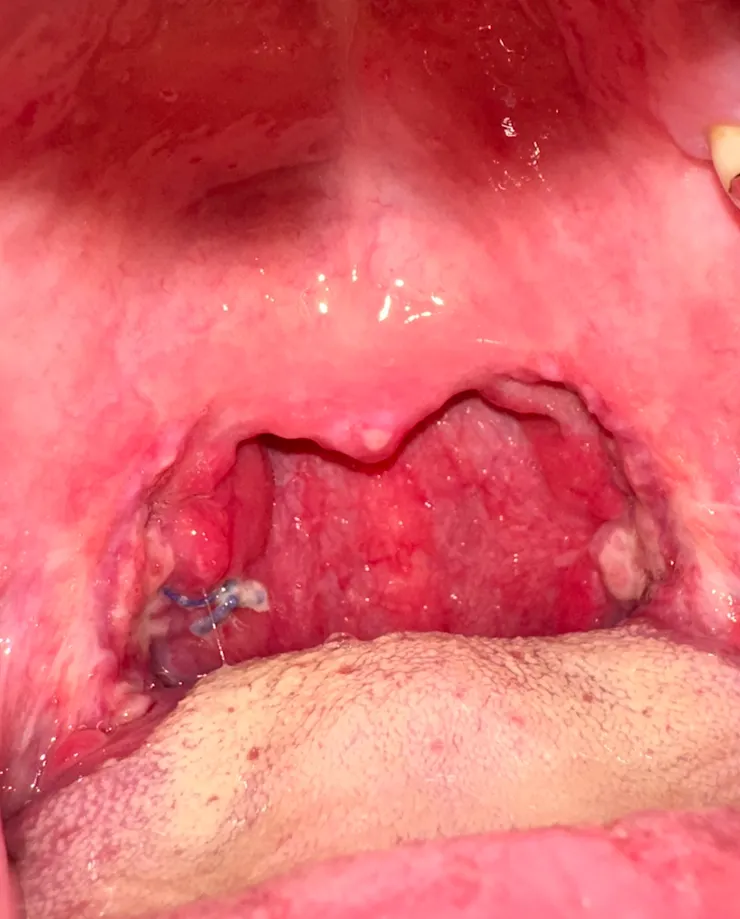

只剩下腫脹 縫線會自行吸收

第11天有了類固醇藥物加持 確實有消腫一些

手術後3週 復原的喉嚨還是有點痛 雖然食物都可以正常吃

3週後已經好差不多了

止痛藥 抗生素 一直吃到3週 回診給醫生看過 就停藥 一切正常了